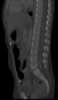

Congenital thoracolumbar vertebral wedging

Congenital vertebral anomalies are a collection of malformations of the spine. Most, around 85%, are not clinically significant, but they can cause compression of the spinal cord by deforming the vertebral canal or causing instability. [Source: Wikipedia ]